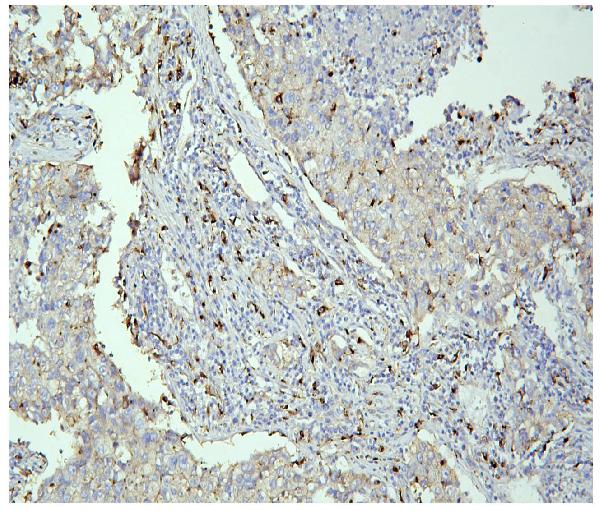

IHC analysis of PPT1 using anti-PPT1 antibody (M02690).

PPT1 was detected in a paraffin-embedded section of human lung cancer tissue. Biotinylated goat anti-mouse IgG was used as secondary antibody. The tissue section was incubated with mouse anti-PPT1 Antibody (M02690) at a dilution of 1:200 and developed using Strepavidin-Biotin-Complex (SABC) (Catalog # SA1021) with DAB (Catalog # AR1027) as the chromogen.